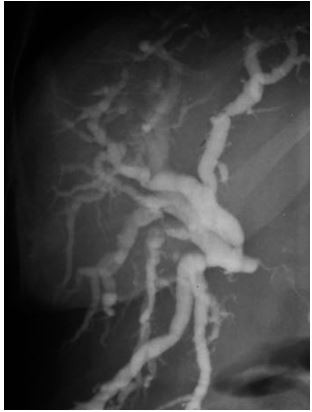

A imagem a seguir é de uma colangiopancreatografia endoscópica retrógrada. Este exame poderia pertencer a todos os pacientes abaixo, EXCETO UM: